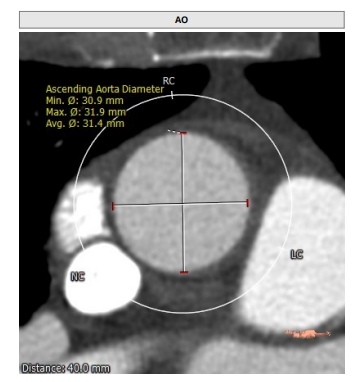

STJ:23.9mm,升主动脉:31.4mm